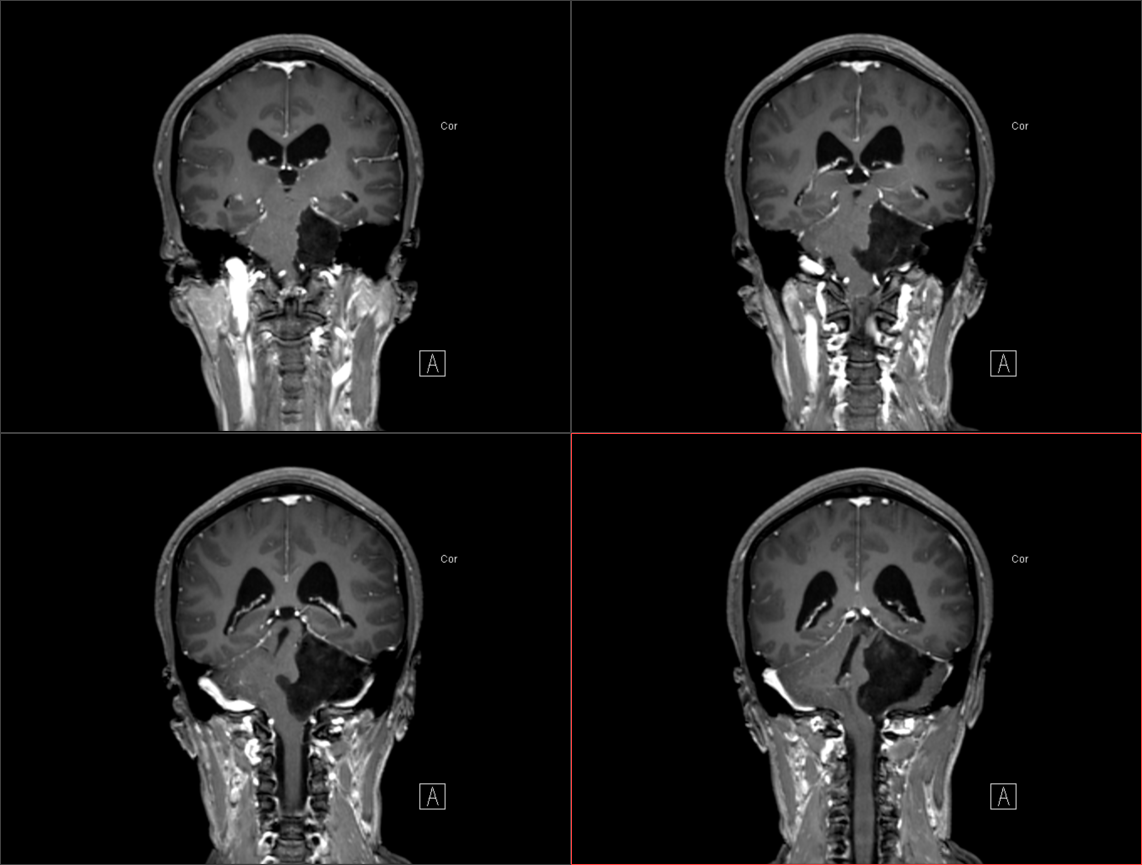

患者于入院前半年无明显诱因出现头痛、头晕,较剧烈,可耐受,无恶心、呕吐,无意识丧失,口服“止痛药(具体药名、剂量不详)”后症状稍缓解,入院前1周上述症状较前加重,患者前往当地医院就诊,行头颅MR示:1.左侧桥小脑角区占位,结合平扫及增强,现多考虑:皮样或表皮样囊肿。2。幕上梗阻性脑积水、脑室轻度积水。3.右侧上颌炎。现转至我院就诊。

术前影像: